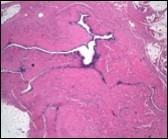

Typically, cutaneous ciliated cyst is a simple cyst which demonstrates a layering of pseudostratified ciliated columnar epithelium recapitulating conventional epithelial lining of the fallopian tube. As the cutaneous ciliated cyst demonstrates a morphological similarity to the fallopian tube lining epithelium, a Mullerian origin is indicated. Gross examination of cutaneous ciliated cyst depicts a solitary, mobile, non-tender, fluctuant, firm or soft to cystic lump with a fibrous wall and abundant amount of circumscribing adipose tissue. Cutaneous ciliated cysts are of a variable dimension. Cut surface usually displays a unilocular cyst impacted with clear, serous fluid, an attenuated smooth, greyish/ white cyst wall incorporated with incomplete septa traversing the cyst 6, 7.

Morphological analysis preponderantly demonstrates a solitary, uni-locular or multi-locular cyst of Mullerian origin with an epithelial lining recapitulating the epithelium of fallopian tube.

Cutaneous ciliated cyst is layered with a singular layer of ciliated epithelial cells which are chiefly constituted by cuboidal to columnar epithelium, traversed by partially configured fibrous tissue septa with an admixture of randomly dispersed, intraluminal papillary projections akin to those cogitated in the fallopian tube. Superimposed epithelium is inundated with well vascularized, parallel bundles of collagen although smooth muscle is absent 7, 8.

Cystic structures cogitated within deep dermal or subcutaneous tissue can be impacted with haemorrhagic fluid. Cyst lining is smooth, regular and is essentially composed of a singular layer of columnar epithelium with focally pseudostratified columnar epithelium, a circumscription of loosely configured, well vascularized, fibroconnective or fibrocollagenous tissue and an absence of inflammatory infiltrate.

Alternatively, cutaneous ciliated cyst can be lined by non ciliated cuboidal or columnar epithelium with intermingled intercalated, dark or round peg cells. Foci of squamous metaplasia can be occasionally exemplified in the adherent epithelium whereas mucinous cells or apocrine-like features are exceptional 6, 8. Figure 1, Figure 2, Figure 3, Figure 4, Figure 5, Figure 6, Figure 7, Figure 8, Figure 9, Figure 10, Figure 11, Figure 12. 11, 12, 13, 14, 15, 16, 17, 18, 19.

Figure 1.Ciliated cutaneous cyst lined by pseudostratified ciliated columnar epithelium and a supporting fibro-connective tissue stroma 11.